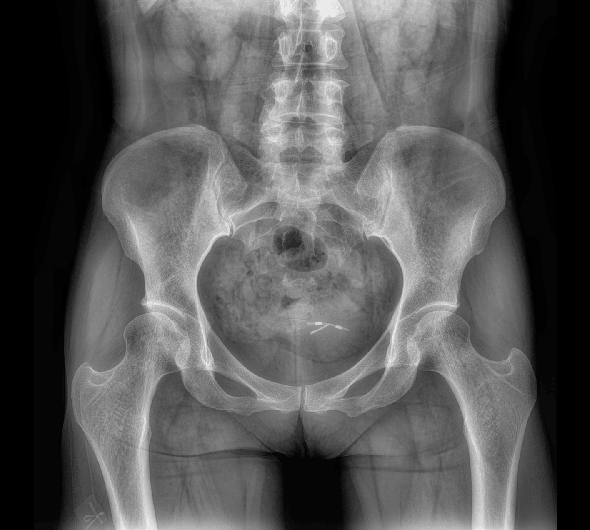

临床图像